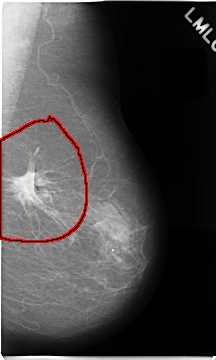

C_0079_1.LEFT_MLO

LEFT_MLO LINES 4672 PIXELS_PER_LINE 2808 BITS_PER_PIXEL 12 RESOLUTION 50 OVERLAY

FILE: C_0079_1.LEFT_MLO.OVERLAY

TOTAL_ABNORMALITIES 1

ABNORMALITY 1

LESION_TYPE MASS SHAPE IRREGULAR MARGINS SPICULATED

ASSESSMENT 5

SUBTLETY 5

PATHOLOGY MALIGNANT

TOTAL_OUTLINES 1

BOUNDARY